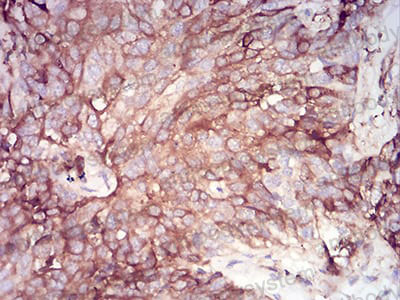

Immunohistochemical analysis of paraffin-embedded human ovarian cancer tissues using SERPINA1 mouse mAb with DAB staining.